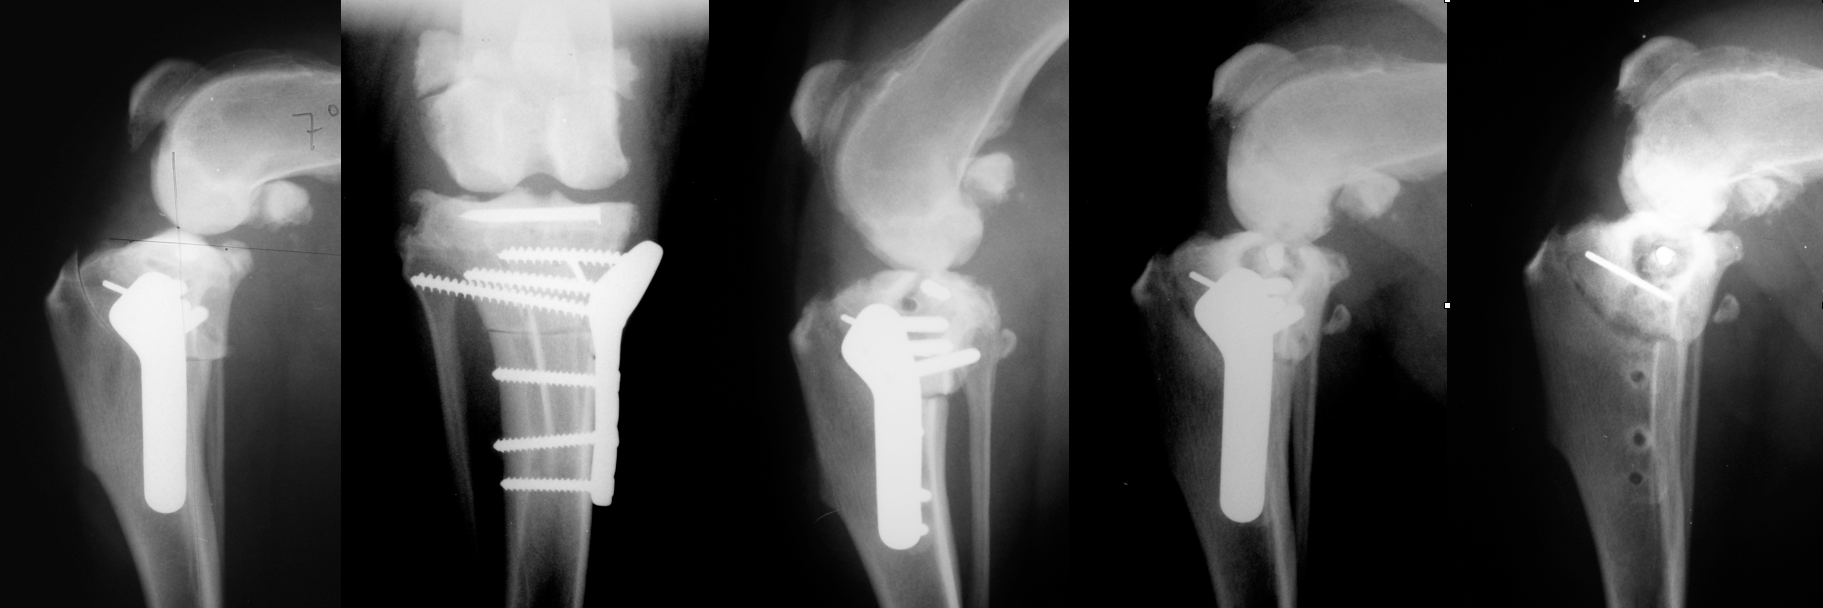

The immediate postoperative radiographic images at the right are examples of precise TPLO planning, excellent limb alignment and ideal orthopedic implants size and position.

Below are four cases of previously operated dogs referred to ACOSM for salvage. Each is an example of poor TPLO techniques and outcomes. In the case of the second series of radiographs, serious intra-operative complications associated with TPLO, a broken jig pin, poor surgical technique and resulting formation of a ring sequestrum resulted in uncontrolled infection and loss of the limb.